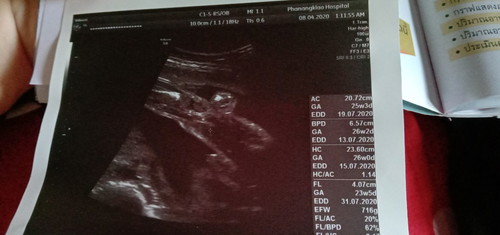

บ้านนี้เห็นมีงวงเล็กน้อยค่ะ😂80%หมอบอกได้ผู้ชาย 18+2

น้องมีไข่ค่ะแม่ 😁😁

ดูไม่เก่งเหมือนกันค่ะ แต่แม่ว่าแม่เห็น นองกางขา แม่ลองเอียงภาพลงทางซ้ายนะคะ